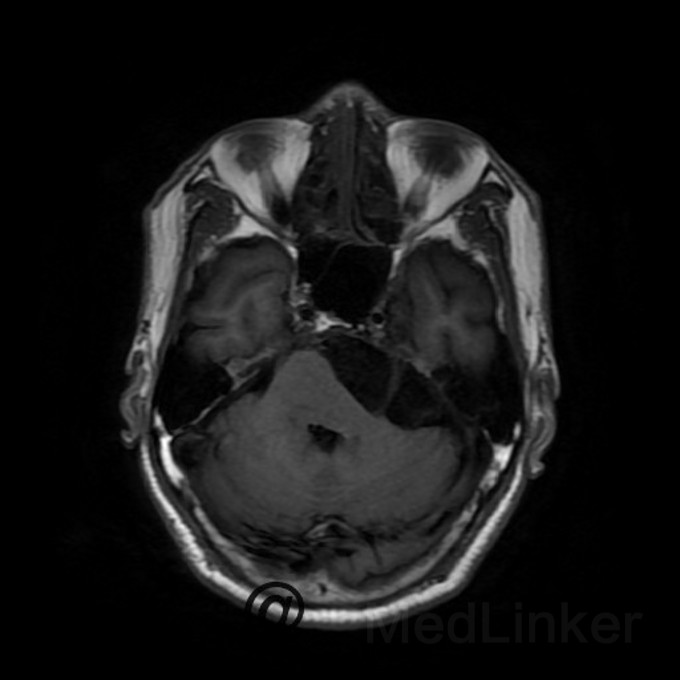

桥小脑区看到一个水样信号影?是蛛网膜囊肿还是表皮样囊肿?

蛛网膜囊肿还是表皮样囊肿都是囊肿,都是T1呈低信号,T2呈高信号,增强都木有强化,两者要怎么鉴别?求赐教

桥小脑区长T1长T2囊状病灶(如图),考虑表皮样囊肿还是蛛网膜囊